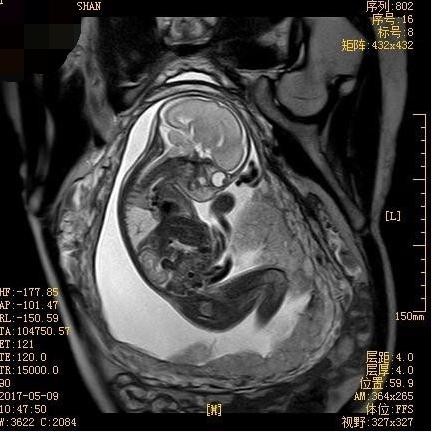

胎儿MRI视野大、软组织分辨率高、不受母体情况如肥胖、子宫肌瘤、羊水过少和多胎等影响,可清晰显示胎儿各个器官信号特点,获得超声不能显示的额外信息,常作为产前超声检查的重要补充手段。近年来,胎儿MRI诊断技术逐渐在临床得到应用并获得重视。胎儿MRI初期主要应用于胎儿神经系统的研究,近年来已经逐渐扩展到胎儿胸部、腹部、盆腔及胎盘等,研究观念从对胎儿单一脏器或系统成像发展为视胎儿为一个整体,这对诊断胎儿多发畸形有重要意义。接下来,我将给大家详细介绍关于胎儿MRI检查的适应症和禁忌症。

中枢神经系统畸形是胎儿MRI最佳适应症,特别是颅后窝畸形,胼胝体发育不良,复杂脑和脊柱畸形,脑室增大原因探查,脑和脊柱肿瘤,脑皮质发育情况评价,神经元移行异常,脑实质缺血或出血,脑、脊髓膨出内容物的鉴别等。

作为我院产前诊断机构的重要组成部分,我科MRI医技护团队积极配合产前超声,开展胎儿MRI检查的各项技术,大大提高胎儿先天畸形的诊断准确性。